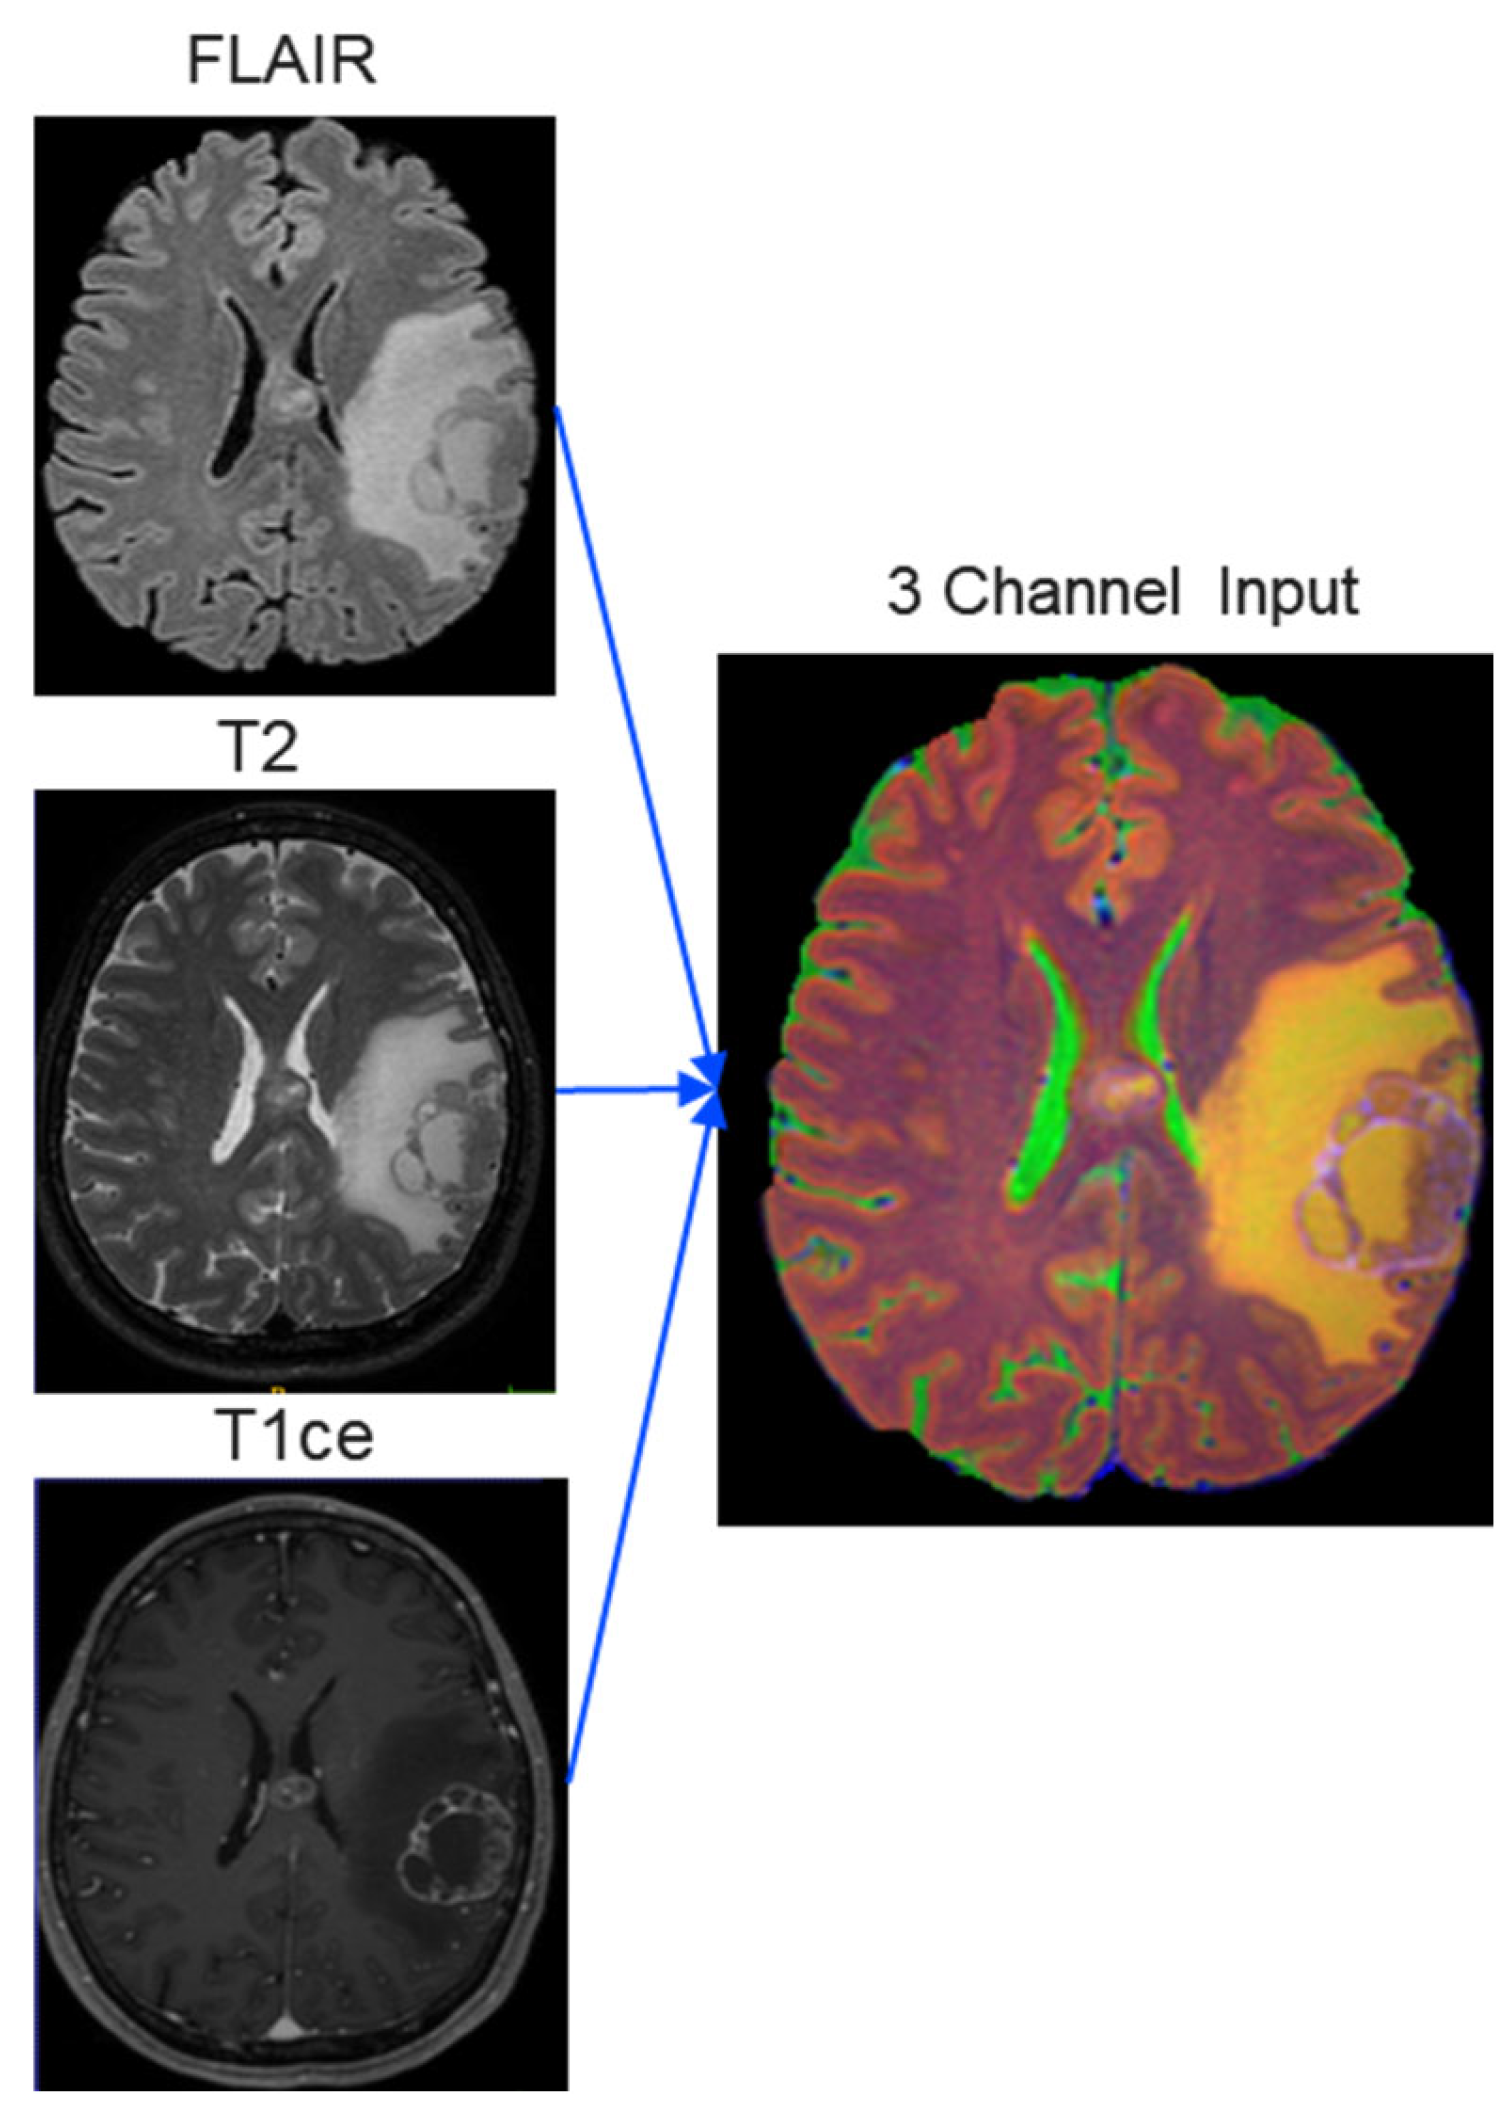

- A hospital-originated dataset incorporating three MRI modalities (FLAIR, T2, and T1ce) and four distinct pathologies: tumors, strokes, multiple sclerosis (MS), and white matter hyperintensities (WMH).

2.2. Image Preprocessing

| Image size | 256 × 256 × 3 |